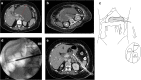

Results and conclusions: An accurate diagnosis should be made a soon as possible, initiating resuscitation with large volume intravenous fluids and oxygen by mask. Predicted severe disease will require intensive monitoring. Most deaths within the first week are due to multi-organ failure; thus, these patients will require intensive therapy unit management. During the second phase of the disease, death is due to local complications arising from the pancreatic inflammation, requiring accurate identification to determine the correct form of treatment. Acute peripancreatic fluid collections arise < 4 weeks after onset of interstitial edematous pancreatitis, not requiring any treatment. Most pancreatic pseudocysts arise > 4 weeks and largely resolve on conservative management. Necrotizing pancreatitis causing acute necrotic collections and later walled-off necrosis will require treatment if symptomatic or infected. Initial endoscopic transgastric or percutaneous drainage will resolve less serious collections but necrosectomy using minimally invasive approaches will be needed for more serious collections. To prevent recurrent attacks of AP, causative factors need to be removed where possible such as cholecystectomy and cessation of alcohol. Future progress requires improved management of multi-organ failure and more effective minimally invasive techniques for the removal of necrosis.